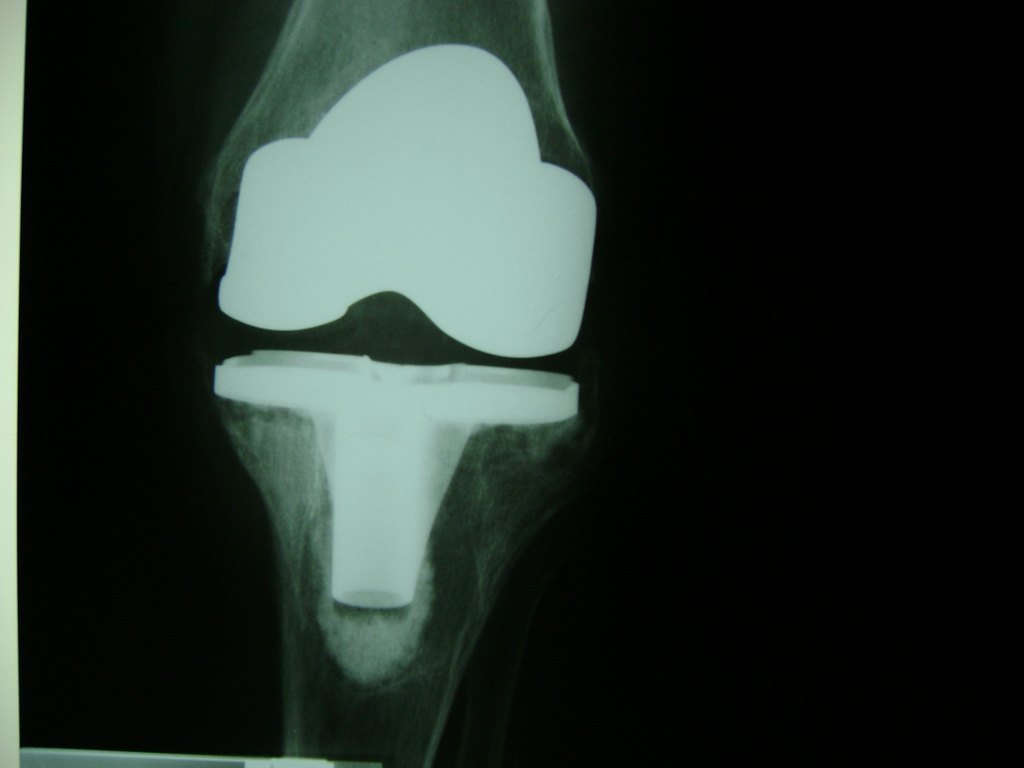

Cirugias en El Salvador - Rodilla

La artroscopia de rodilla es un cirugía en el cual la estructura interna de la articulación es examinada ya sea para realizar un diagnostico o para realizar un tratamiento, este procedimiento se realiza utilizando un instrumento parecido a un pequeño tubo llamado artroscopio.